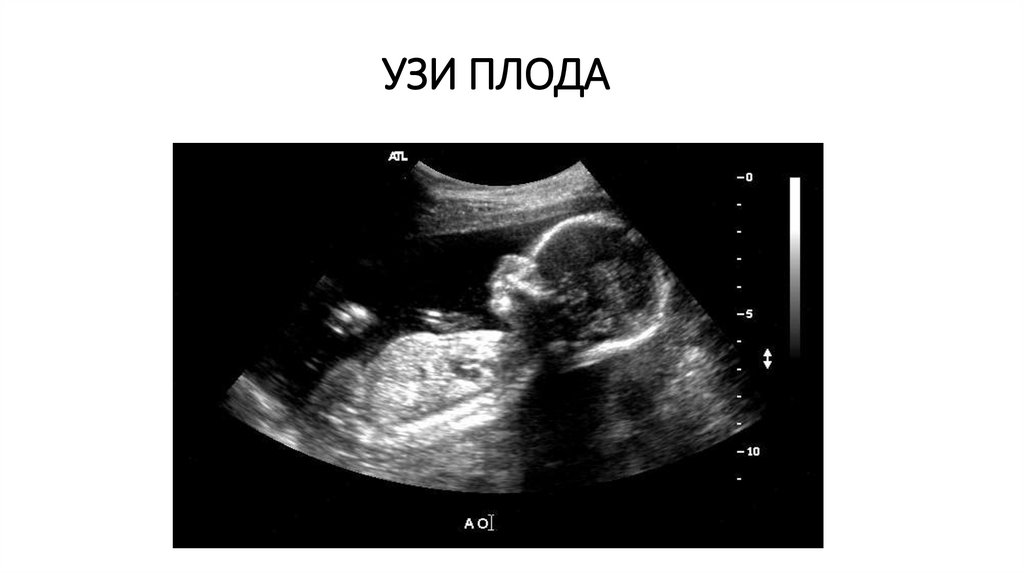

УЗИ ПЛОДА

17. УЗИ ПЛОДА

Плод и плацента: определение срока беременности, многих аномалий развития плода, его функционального состояния